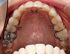

Чи можна вирівняти такі зуби пластинкою?

26 років. В принципі воно мені не критично, але зайнялась здоров’ям зубів і думаю може вже і це виправити. Хто в дорослому віці носив, вони допомогли вам?

Брекети точно не хочу. Розглядаю хібащо пластинки.

у вас проблема не на уровне зубных рядов, у вас узкая верхняя челюсть, при улыбке не видно четверки. т.е надо ортодонтическими апаратами расширить верхнюю, а потом брекетами подогнать оклюзию.

насчет пластинки, я лечилась у ортокраниодонта и носила такого плана пластинку, как ставят детям, но у меня было односторонне расширение, одна сторона была сужена и опущена. и пластинка реально работает,челюсть расширилась и почти выровнялась, но потом надо носить ретенционную для закрепления, все это очень долго. и самая главная проблема, что потом всеравно надо делать полное смыкание, и без брекетов или спиливания собственных зубов, это сделать нельзя. поэтому не нужная вам такая пластинка. возможно ортодонт предложит по другому расширить вч и сделать нормальную окклюзию

не хочу нічого розширювати, тільки порівняти. місце куди то все штовхати є, бо видалили всі 4 вісімки.

Пластина только расширяет. У детей зубы выравниваются из-за того что появляется для этого место.

Вам без принудительного давления расставить ровно зубы в нужных местах челюсти не получится.

Ваши со временем чуть расползутся за счет удаленных 8-к, но шире верхняя челюсть не станет, а расширение явно просится судя по фоткам.